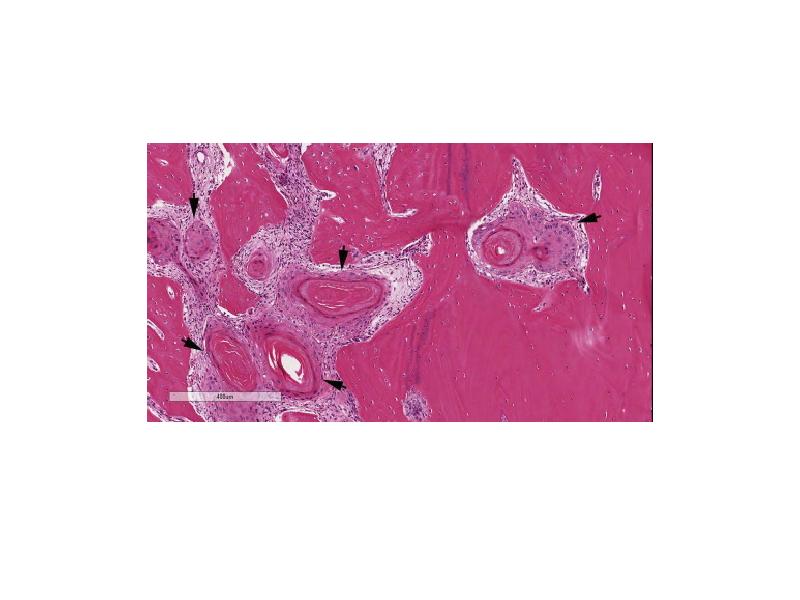

- 69. Костная дисплазия (периапикальная цементодисплазия) Встречается в области верхушек нижних резцов в

- 71. Формы/названия Периапикальная костная дисплазия – поражение возникает в передней части нижней

- 72. Гигантоморфная цементома Характеризуется мультицентричным ростом с образованием многочисленных узелков и узлов

- 73. Исходы Периапикальная и очаговая костная дисплазия обычно являются случайными рентгенологическими находками.